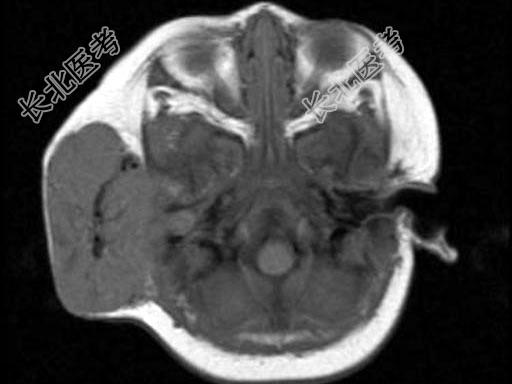

- 单项选择题老年患者,右侧面部肿胀, 呈青紫色,MRI检查如图所示, 最可能的诊断是 ( )